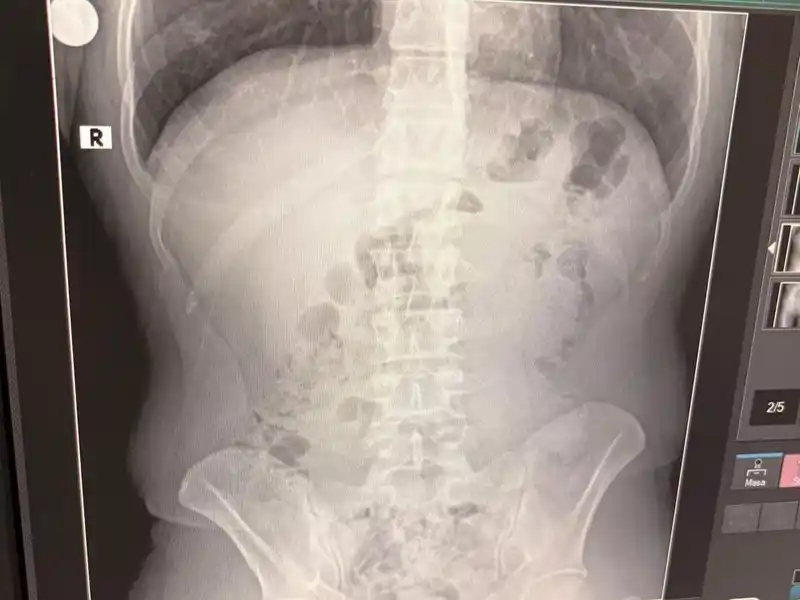

Adreste yapılan arama sırasında ekipler, şüphelilerden birinin üstünde 1 adet kapsül ele geçirdi. Şüphe üzerine tüm şüpheliler hastaneye götürüldü ve yapılan röntgen kontrollerinde 3 kişinin midelerinde kapsül içine gizlenmiş metamfetamin tespit edildi.

Hastanede tedavi altına alınan şüphelilerin vücudundan kapsüller çıkarılırken, adreste ele geçirilenlerle birlikte toplam 1 kilo 516 gram metamfetamin ele geçirildi.